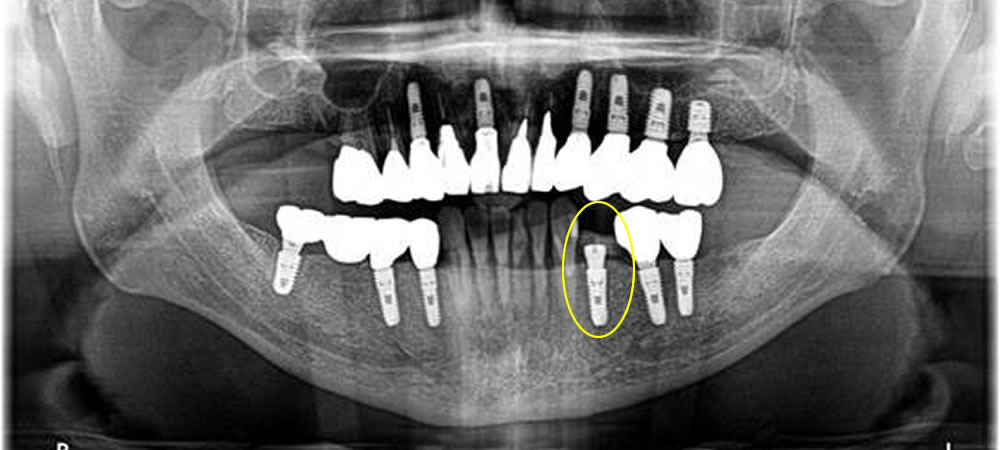

インプラント手術の実施

歯を支えている骨の損傷が大きかったため、骨造成(骨を増やす処置)も追加で行いました。支えがないとせっかく打ったインプラントもしっかり固まらないため、骨造成が効果的なケースがあります。